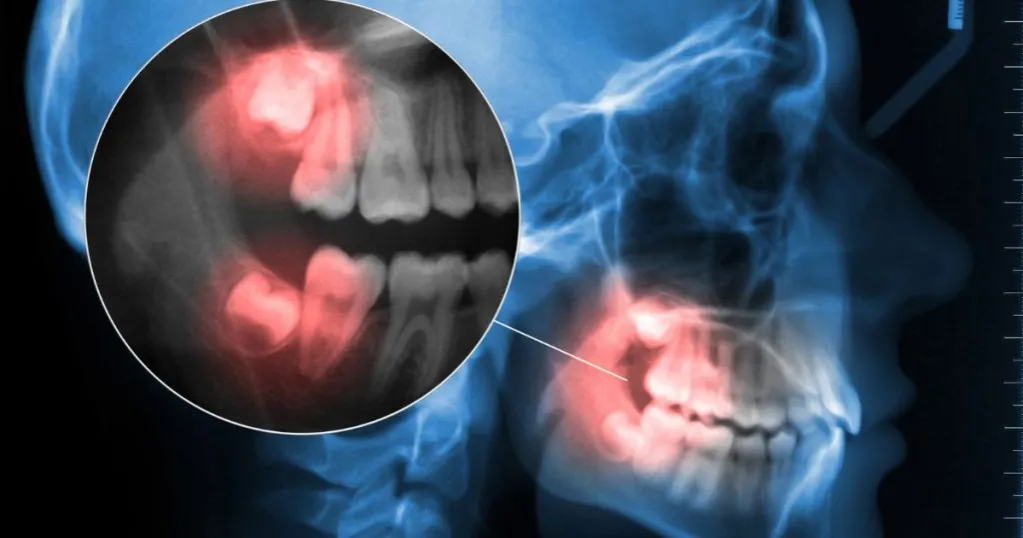

Problem z "sąsiadem": jak zachowuje się siódemka po utracie podparcia?

Ząb sąsiadujący bezpośrednio z usuniętą ósemką, czyli siódemka, może zareagować na utratę podparcia w sposób niekorzystny. Bez nacisku i stabilizacji ze strony ósemki, siódemka ma tendencję do przechylania się w stronę pustego miejsca. Takie przechylenie może prowadzić do zaburzeń zgryzowych, nieprawidłowych kontaktów z zębami przeciwstawnymi, a także utrudniać higienę, zwiększając ryzyko próchnicy i chorób przyzębia w tej okolicy.